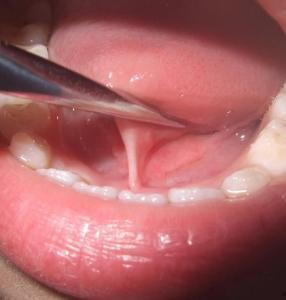

首先,得先弄清楚什么是舌系带。舌系带,简单来说,就是连接舌头底部和口腔底部的一条筋膜。有些人因为舌系带过短,导致舌头活动受限,说话发音不清,甚至吃饭都成问题。这时候,医生就会建议进行舌系带修剪手术。

2. 手术过程:手术通常在局部麻醉下进行,医生会使用手术刀将舌系带剪断,然后进行缝合。